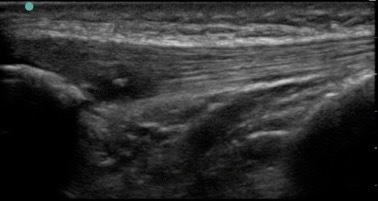

Knee Under Surface Patellar Tendon Tear Image